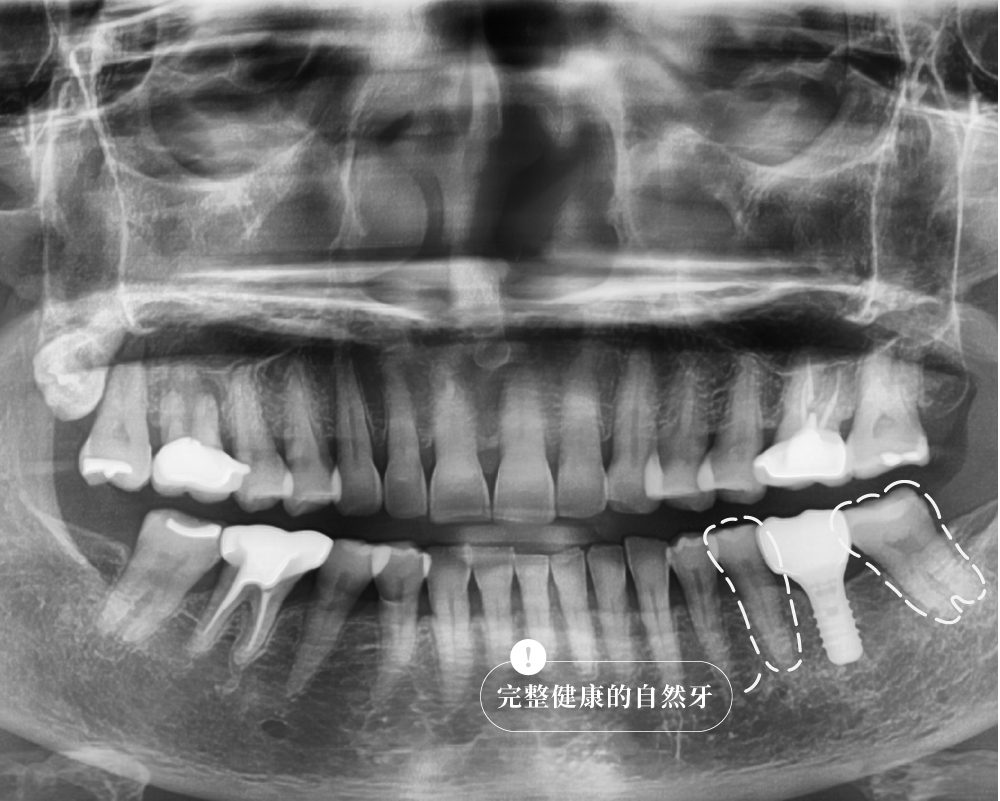

案例解析:L先生的右下第一大臼齒咬裂

治療前:牙齒疼痛疑似有牙根斷裂

治療後:單顆植牙恢復咬合